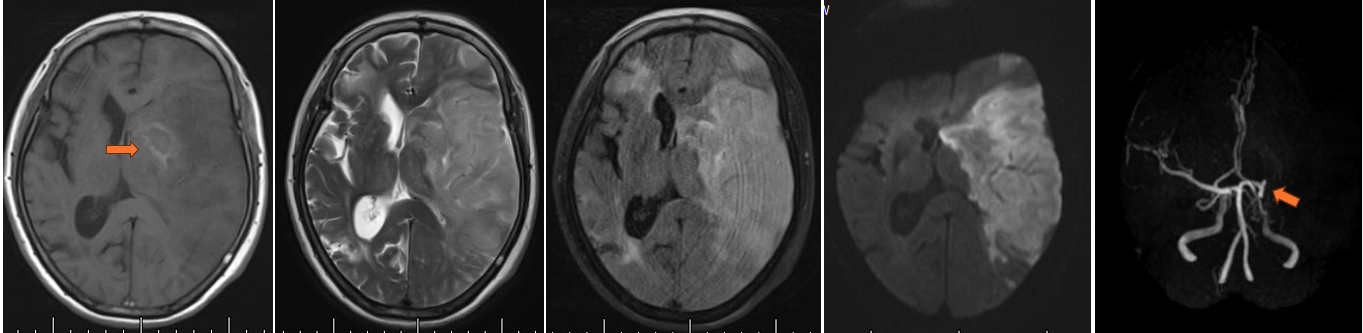

李x,反复发作性意识障碍伴肢体抽搐20余年

一、病例特点1、患者青年男性,慢性反复发作性病程;2、临床表现具有不同发作形式,其一、意识丧失伴肢体抽搐;其二、转颈伴双上肢漫无目的摸索或其它活动;3、查体:神志欠清,言语及认知查体不合作,突出认知障碍。四肢肌力查体不配合,肌张力适中,双侧巴氏征未引出,脑膜刺激征阴性。4、患者父母提供病史,自3岁时发现孩子出现抽搐情况,曾就诊于北京x医院,给予抗癫痫药物治疗,近半年药物不能有效控制病情,一月发作数次;患者形体肥胖,认知障碍突出,智商明显低于同龄人。5、辅助检查:凝血5项:D-二聚体:0.52mg/L,↑;肝肾功能+电解质+心肌酶:γ-谷氨酰转肽酶:108U/L,↑尿酸:446μmol/L,↑钾:3.35mmol/L,↓;血常规正常;血气分析:氧分压:79.3mmHg,↓ 二氧化碳分压:33.4mmHg,↓标准碳酸氢根:23.2mmol/L,↓细胞外液剩余碱:-2.4mmol/L,↓离子钙:1.10mmol/L,↓阴离子间隙:20.3mmol/L,↑ 葡萄糖:5.70mmol/L,↑ 乳酸:2.67mmol/L,↑;心梗二项、BNP、PCT正常;头胸CT:胸部CT平扫未见异常;肝脏、左肾多发低密度灶,肝脏下方含脂肪病变,建议进一步检查;二、神经影像 {x} 头CT(2024-03-28 我院):脑室内见多个结节致密影。三、临床印象{alert type="info"}结节性硬化相关性癫痫{/alert}四、临床诊治 1、调整饮食结构,生酮饮食。适用于各种癫痫类型,尤其是难治性癫痫。生酮饮食可有效地降低结节性硬化相关性癫痫的发作频率,但效果随着时间延长而下降,生酮饮食停止后癫痫会再次发作。 2、改善营养状况,纠正内环境紊乱。机体营养障碍及内环境紊乱是癫痫控制不佳的常见原因,值得大家重视。 3、调整AEDs方案,患者院外抗癫痫方案为:奥卡西平片 0.3g 2次/日,左乙拉西坦片 1.5g2次/日。癫痫发作临床控制不佳,需完善血药浓度检测,结果提示OXC 20.18ug/mL(参考值10~35),LEV 41.71ug/mL(参考值 10~40),化验结果提示血药浓度达到有效水准,无需增大方案剂量! 4、建议在上述方案基础上增加苯巴比妥溴化钠片,患者体型肥胖,给予1片 3次/日,2日后患者癫痫发作得以控制; 5、查阅文献,结节性硬化(TSC)相关性癫痫发病率国外文献竟高达83.6%,且多为难治性癫痫。推荐药物及外科手术治疗,手术治疗需严格把控适应症,费用昂贵。在考虑手术之前药物方案仍为首推治疗方法,具体药性特点及注意事项见下: - ★ 氨己烯酸:是TSC相关性婴儿痉挛和/或局灶性癫痫一线治疗单药及局灶性难治性癫痫的辅助用药。氨已烯酸能够安 全有效地缩短癫痫发作的时间,降低癫痫及婴儿痉挛的发生率和严重程度。氨已烯酸的治疗效 果具有剂量依赖性,高剂量的氨已烯酸能够更有效 地降低婴儿痉挛复发率,长期服用治疗效果会减退。对于单用氨已烯酸治疗效果不理想的患者, 可以联合皮质类固醇或其他抗癫痫药物作为二线治疗方案。氨己烯酸对视网膜存在不可逆的毒副作 用,其发生率会随着治疗时间的延长及药物剂量的 增加而升高,服药期间应该定期行视力视野检查。 - ★ 大麻二酚:主要用于 Lennox-Gastaut 综合征相关的癫痫、Dravet综合征、1 岁及以上TSC患者癫痫的治疗。治疗剂量的大麻二酚能够显著降低 TSC 相关性癫痫尤其是难治性癫痫的发作频率。大麻二酚可升高依维莫司血药浓度,合用时需要定期监测依维莫司血药浓度。腹泻、食欲减退和嗜睡是大麻二酚使用过程中最常见的不良反应。 - ★ 其他经典抗癫痫药物:除氨己烯酸、大麻二酚外,还有一些经典抗癫痫药物如丙戊酸钠、左乙拉 西坦、卡马西平、拉莫三嗪、托吡酯、奥卡西平、拉科 酰胺等也可用于TSC相关性癫痫的治疗。目前研究最多的是布瓦西坦,一种新型的吡咯烷酮衍生物类抗癫痫药,具有更高的SV2A蛋白选择性和结合力、更快的脑组织渗透速度、更低的有效血药浓度、更高的治疗指数及更强的抗癫痫潜力。因其更好的治 疗效果和更低的不良反应发生率,被批准用于4岁及以上局灶性癫痫患者的辅助治疗。 - ★ mTOR抑制剂:依维莫司作为雷帕霉素40-O-2 -(羟乙基) 衍生物是目前研究最多的 mTOR抑制剂,具有更高的血脑屏障穿透性、水溶性、生物利用度和更短的半衰期。依维莫司作为辅助治疗药物能够安全有效地降低TSC相关的难治性癫痫的发作频率。依维莫司的治疗效果具有时间和浓度依赖性停药后癫痫可再次发作。口腔炎、腹泻、鼻咽炎、发热和上呼吸道感染是依维莫司 常见的不良反应,必要时需要及时调整药物剂量并给予对症支持治疗。